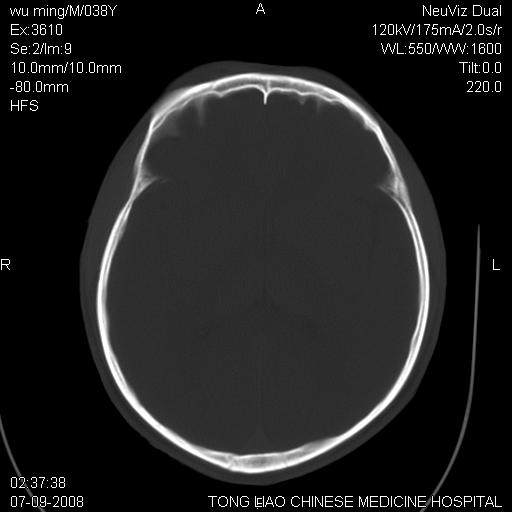

面骨、颅底骨多发骨折,右侧硬膜下小血肿,弥漫轴索损伤,死亡原因可能是多种因素致。

颅底骨折,窦腔内积血。考虑死亡原因为脑水肿压迫脑干或因大量失血死亡。

多发性颅骨骨折

考虑:面骨、颅底骨多发骨折。从五楼摔下还伤着头了,不死才怪;估计有弥漫性轴索损伤。